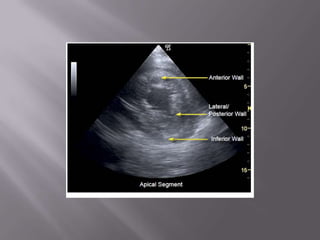

Ferramenta não apenas diagnóstica como de monitorização  Fundamental na abordagem do choque e da dispnéia  Permite em segundos descartar embolia pulmonar e tamponamento cardíaco como causas do choque  Usado na PCR – determinar causa reverível – durante a checagem do Pulso!  Transtorácico ou Transesofágico?